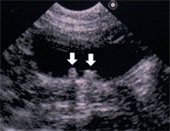

腹膜透析

専用のカテーテルを動物の体に設置して、透析液をお腹に入れるルートをつくります。

透析液をお腹に入れ、腹膜を介して体内の老廃物などを透析液に回収・排出する事で、

尿毒症を改善する治療法です。